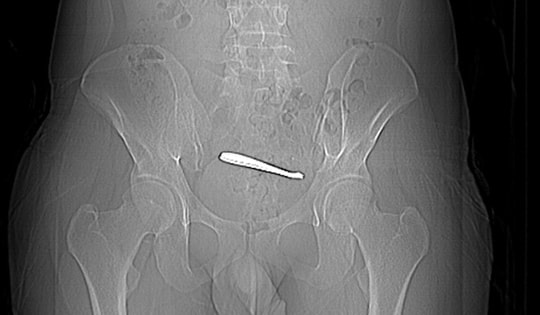

Một thiếu niên 15 tuổi phải nhập viện cấp cứu trong tình trạng đau dữ dội sau hành động bồng bột do tò mò. Thăm khám cho thấy có dị vật mắc kẹt trong cơ thể.